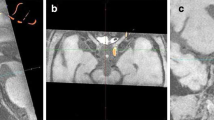

Excessive insertion of the filament tip can cause the rupture of intracranial vessels and hemorrhagic complications. The A1 segment of ACA is the predominant injury location, because it is thinner than the distal part of ICA, it bends to merge with the opposite ACA to form common (azygos) anterior cerebral artery, and the filament tip is too thick to fit its inner diameter. MRI images of intracranial hemorrhagic complications after excessive filament insertion are shown on Fig. 3a, b. In our experiments, subarachnoid hemorrhages (SAH) were the most frequent of the observed complications. Normally, the subarachnoid space between the arachnoid membrane and the pia mater contains CSF, which is hyperintense on hrT2wi. In case of SAH, the subarachnoid space becomes replete with blood which is hypointense on the T2wi and SWI as illustrated by Fig. 3a. A particularly deep insertion of the filament can cause subdural hemorrhage appearing as a crescent-shaped mass consisting of liquid and clotted blood between the dura mater and arachnoid mater and leading to brain dislocation (Fig. 3b). Rupture of cerebral blood vessels causes severe vasospasm (Fig. 3a, MIP hrT1wi), which in turn may trigger ischemic stroke (usually in the MCA and the ACA vascular territories as shown in Fig. 3c) mimicking successful MCAO. In our experiments, animals with intracerebral bleeds combined with ischemic stroke exhibited more severe neurological symptoms (including seizures, meningeal signs, impaired consciousness) than rats after correctly performed MCAO (unpublished results). Animals with hemorrhagic complications were excluded from the study immediately after MRI.

Hemorrhagic complications of MCAO after excessively deep filament insertion. a Subarachnoid hemorrhage (SAH). On T2wi, the normal hyperintense signal from the cerebrospinal fluid (CSF) filling the subarachnoid space and cisterns turns into the hypointense signal due to the replacement of CSF with blood (red arrows on hrT2wi, red on scheme). SAH also can be visualized on SWI (red arrow on SWI) and, partly, on hrT1wi (red arrow in hrT1wi). The most common cause of SAH during MCAO is the rapture of the A1 segment of ACA by the filament tip, which in turn causes vasospasm—on MIP hrT1wi right MCA, and the distal part of ICA is not visualized. b Subdural hemorrhage (SDH). Subdural hemorrhage, often leading to brain dislocation, can be visualized as a heterogeneous crescent-shaped mass between the dura mater and arachnoid mater (red arrows on hrT2wi and T2wi). c Ischemic stroke after rupture of the left ACA by the filament tip. ADC is low not only in the MCA but also in the ACA (red arrow on ADC) vascular territories. SAH visualized on T2*wi as hypointense area in the skull base (red arrow on T2*wi)